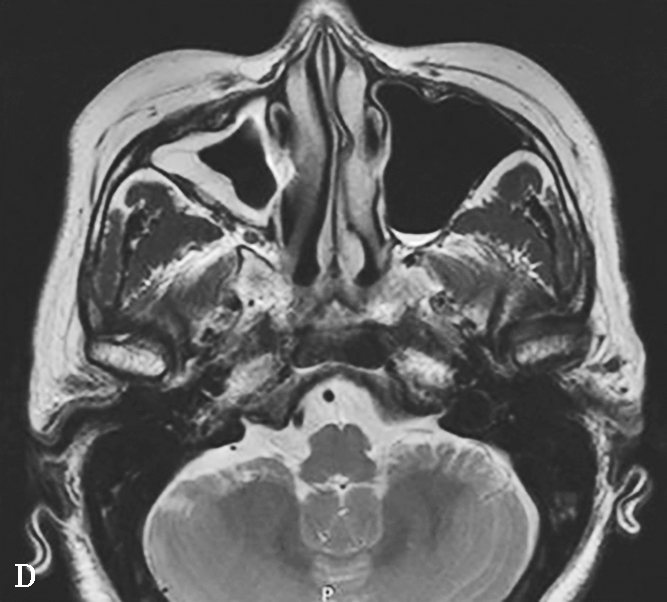

图1-3-25 慢性侵袭性真菌性鼻窦炎

A、B.横断面CT及冠状面CT骨窗,示右侧蝶窦可见软组织影充填,蝶窦侧壁欠光整,骨皮质略模糊;C.横断面T 2 WI,示右侧蝶窦病变呈混杂等略低信号,右侧海绵窦受累增厚;D.横断面T 1 WI,示病变呈略高信号;E.横断面T 1 WI+FS+C,示蝶窦腔病变大部分无强化,可见不规则索条状明显强化影,窦腔边缘黏膜增厚强化,右侧海绵窦受累增厚强化,斜坡及Meckel腔脑膜增厚强化;F.冠状面T 1 WI+FS+C,示蝶窦病变破坏鞍底骨质,累及鞍上及右侧海绵窦,垂体受累轻到中度不均匀强化,蝶窦黏膜弥漫性增厚强化